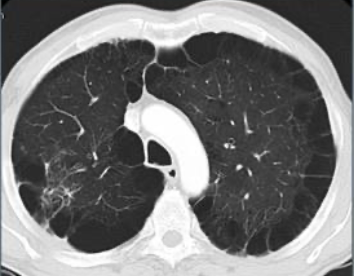

Que imagen distingue distribución en EPOC enfisematoso?

TC

Centrolobulillar